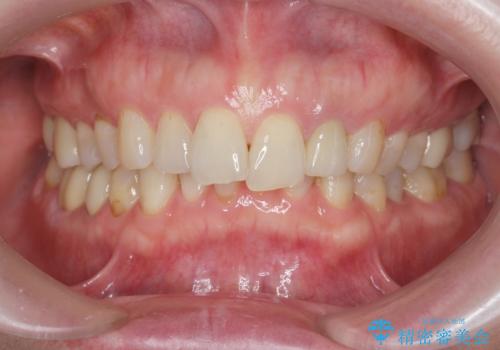

治療後、明るくなった口腔内を見て大変満足いただくことができました。

色調だけでなく、精密な治療を行うことで虫歯の再発の確率を下げることも可能になります。